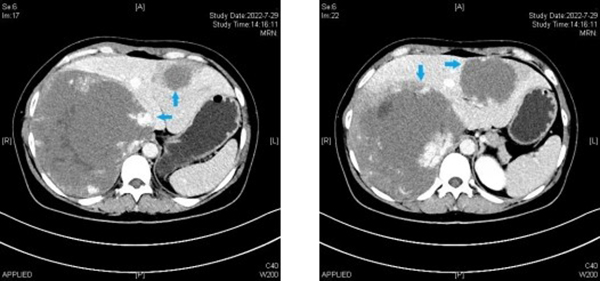

臨床上,病灶直徑10㎝以上就屬于巨大肝血管瘤。本例患者肝血管瘤共兩枚,分別位于肝左右葉,其中肝右葉瘤體直徑超過20cm,而肝左葉瘤體直徑也達(dá)到9cm,瘤體總體積甚至遠(yuǎn)超殘余肝臟體積。而右葉瘤體又發(fā)生于肝臟S7、8段,是腹腔鏡肝臟手術(shù)最困難的區(qū)域。由于瘤體巨大,壓迫膈肌,致膈肌上抬,同時擠壓人體最粗的血管下腔靜脈和腹主動脈,使其受壓變形并移位。瘤體在肝內(nèi)則緊鄰菲薄的右肝及中肝靜脈,并且與入肝血流的門戶——第一肝門關(guān)系密切。術(shù)中一旦損傷上述血管,就會導(dǎo)致難以控制的大出血,氣體栓塞,肝功能衰竭等危及生命的并發(fā)癥。同時由于瘤體巨大,在手術(shù)切除瘤體過程中又要盡量保留正常肝臟組織的體積及功能。患者既往有兩次婦科手術(shù)史,腹腔粘連也是微創(chuàng)手術(shù)操作的攔路虎。但考慮到患者是年輕女性,對美觀及微創(chuàng)有著強(qiáng)烈的愿望。劉斌、魏鑫團(tuán)隊在進(jìn)行充分評估及術(shù)前準(zhǔn)備后仍決定為患者實施腹腔鏡手術(shù)。2022年8月2日,手術(shù)在馬萬林麻醉團(tuán)隊低中心靜脈壓控制、自體血回輸?shù)谋U舷潞投规面玫茸o(hù)理團(tuán)隊的精準(zhǔn)配合下取得了圓滿成功;颊咝g(shù)后第一天即下床活動進(jìn)并進(jìn)食流質(zhì)飲食,1周后拔除引流管出院。